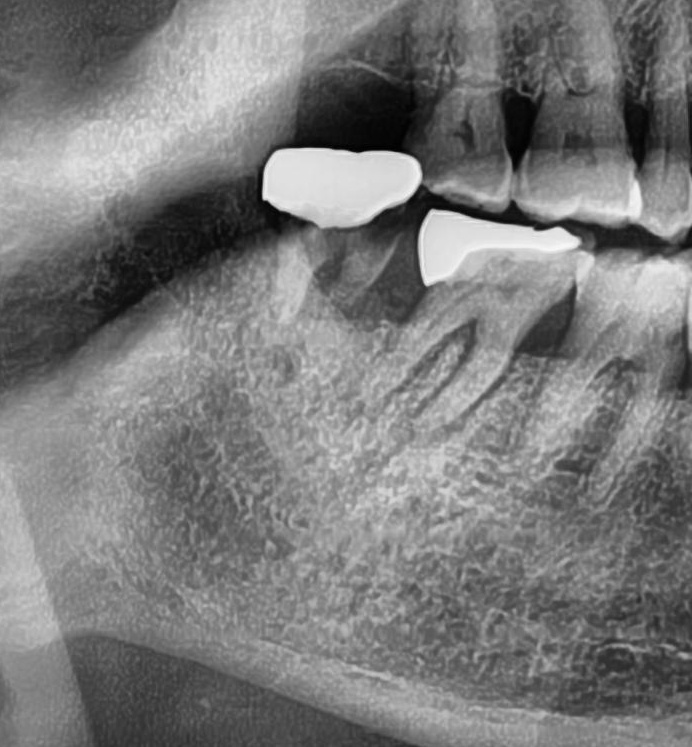

次にパノラマ写真を撮影してみると、親知らずはまっすぐに生えているのが確認できました。

親知らずが生えている位置が、神経に近い、あるいは神経に当たっている場合は、大きな病院に紹介する場合もあります。

親知らずの根っこは下歯槽神経からも十分距離があり、抜歯は可能との診断でした。